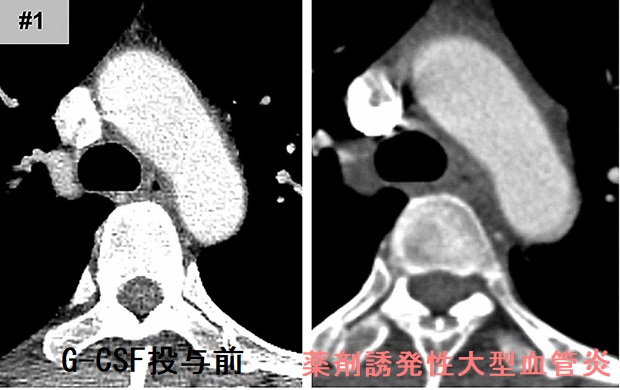

甲状腺機能亢進症/バセドウ病治療薬、抗甲状腺薬(メルカゾール、プロパジール、チウラジール)の最も恐ろしい副作用である無顆粒球症(好中球という白血球が激減し免疫不全におちいる状態)には、G-CSF(顆粒球コロニー形成刺激因子)製剤を投与します。G-CSF製剤の重大副作用に薬剤誘発性大動脈炎(薬剤誘発性大型血管炎)があり、大動脈炎症候群(高安病)と画像上似ているため鑑別を要します。[G-CSF(顆粒球コロニー形成刺激因子)製剤と甲状腺](Mod Rheumatol Case Rep. 2020 Jan;4(1):74-78.)

(薬剤誘発性大型血管炎 造影CT画像 Sci Rep. 2020 Oct 29;10(1):18647.)